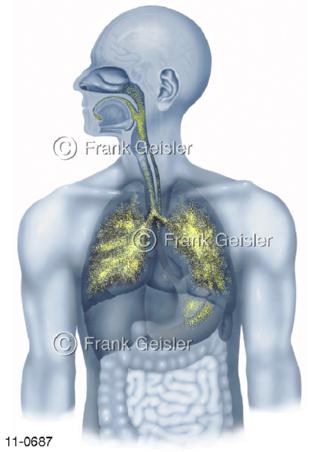

11-0687 Atemtrakt, Atemwege mit Lunge, Aerosolverteilung